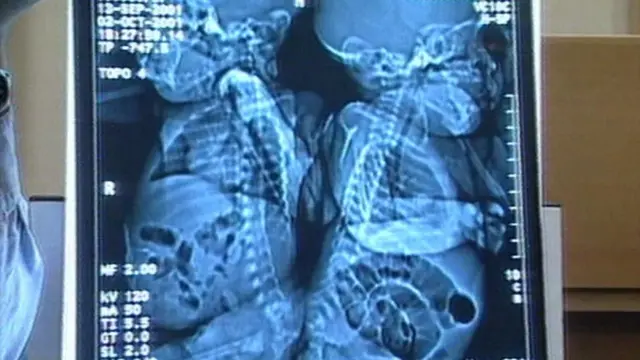

బ్రిటన్లోని బర్హింగ్హమ్లో 19 ఏళ్ల క్రితం ఓ అరుదైన శస్త్ర చికిత్స జరిగింది. అవిభక్త కవలలు (శరీరాలు అతుక్కుని పుట్టిన సయామీ కవలలు) సంచియా, ఎమాన్ మోవాట్లను వైద్యులు కష్టపడి విడదీశారు.

అప్పటికి ఆ చిన్నారుల వయసు మూడు నెలలే. వాళ్లద్దరి శరీరాలు వెన్నెముక మొదలు భాగంలో అతుక్కుని ఉన్నాయి.

2001 డిసెంబర్లో 16 గంటల పాటు వైద్యులు శ్రమించి వారిని వేరు చేశారు. బ్రిటన్లో అలాంటి శస్త్ర చికిత్స జరగడం అదే మొదటిసారి. ప్రపంచంలో మూడోసారి.

సంచియా, ఎమాన్ల శరీరాలను విడదీసే శస్త్రచికిత్సను న్యూరో సర్జన్ టోనీ హోక్లీ నేతృత్వంలోని వైద్య బృందం చేసింది. అతుక్కుపోయిన వెన్నెముక, మూత్రాశయం సహా కొన్ని అవయవాలను విడదీసింది.

సంచియా, ఎమాన్లకు అవయవాలు పూర్తిగా ఏర్పడ్డా, అవి అతుక్కుని ఉన్నాయి.

వెన్నెముకలు వేరు చేసిన తర్వాత పీడీయాట్రిక్ సర్జన్ పీటర్ గోర్నల్, అవిభక్త కవలల వైద్యంలో బాగా పేరు తెచ్చుకున్న లూయిస్ స్పిట్జ్ కలిసి మిగతా అవయవాలను వేరు చేసే ప్రక్రియలు పూర్తి చేశారు.

‘‘ఆ ఇద్దరు పాపలకూ వెన్నెముకలు ఉండేలా మేం కోత పెట్టాలి. దాని చుట్టూ కవచం కూడా ఏర్పాటు చేయాలి. కోత పెట్టడం పాత పద్ధతే. కానీ, ఎక్కడ కోత పెట్టాలన్నది తెలుసుకోవడమే సవాలు’’ అని ఆ శస్త్ర చికిత్స చేసిన తర్వాత హాక్లీ వ్యాఖ్యానించినట్లు ‘ద గార్డియన్’ పత్రిక రాసింది.